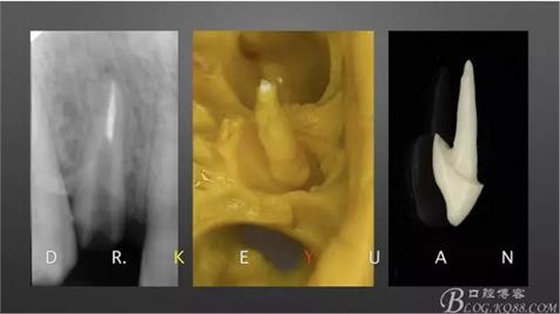

CASE 4—18歲少年,冠折后半年來診

0、根管治療(千里之行始于根下)

1、術(shù)前比色

3、取硅橡膠模型制作氧化鋯樁

4、粘接氧化鋯樁